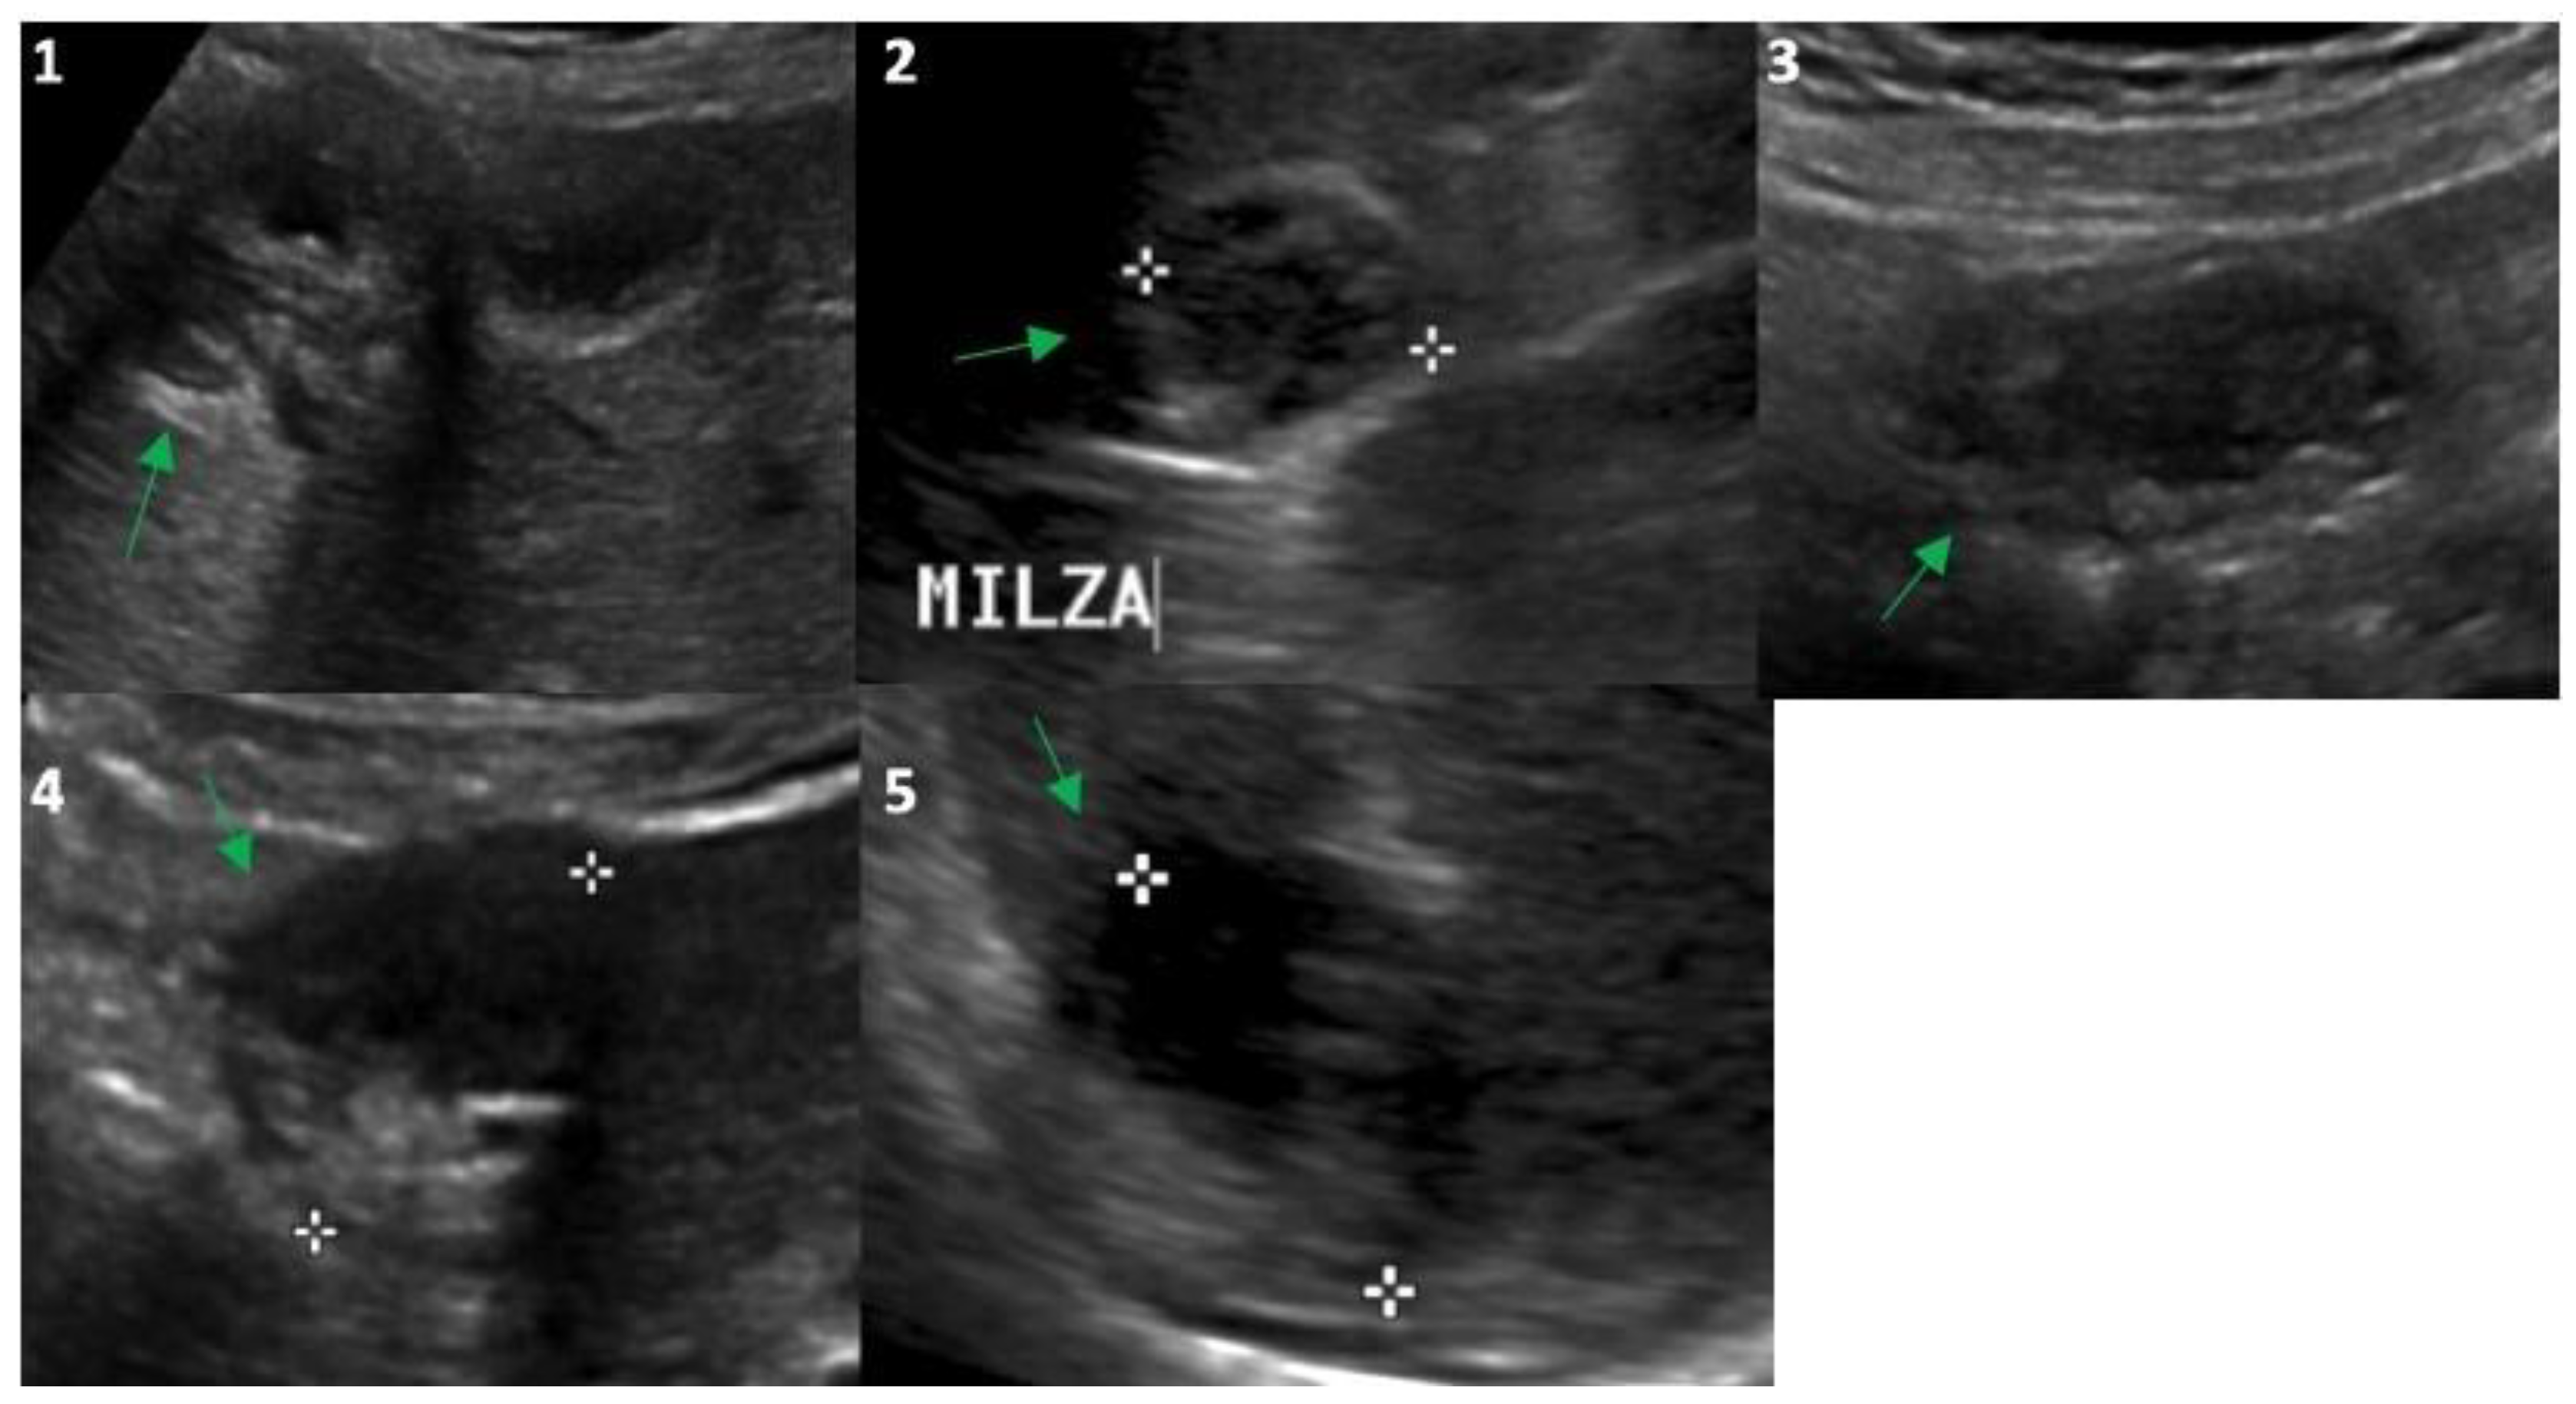

Figure 2.

Ultrasound evaluation in 2023 of the Echinococcus cysts (green arrows) presented in Figure 1: segment 5 of the liver (frame (1); 25 mm), upper pole of the spleen (frame (2); 26 mm), right inframesocolic space (frame (3); 36 mm), segment 3–4 (frame (4); 30 mm) and 6 (frame (5); 30 mm) of the liver. White asterisks correspond to the points of the echo-calipers used to measure the size of the cysts.

In 2014, the anti-Echinococcus titers were still elevated, serum AST, ALT and GGT were normalized and imaging of the cysts suggested possible activity especially for the peritoneal localizations; therefore, treatment with ABZ was re-started and continued until 2021. Normal hepatic blood test results were observed until the end of treatment with ABZ in 2021 (Table 1) and a final (2021) hepatic FibroScan demonstrated normal stiffness values (May 2021, 2.8 kPa). We observed no significant change in the eosinophil count for the whole duration of the follow-up (Table 1), thus excluding a significant relationship between eosinophilia in this case of cystic echinococcosis [10]. Finally, at the end of 2021, the patient had received a total of 15 complete cycles with ABZ that equaled 1260 days of treatment. All cystic lesions progressively showed US [11] and CT signs of regression (Figure 1 and Figure 2) with some uncertainty for peritoneal lesions, which are still in follow-up in 2023. In particular, based on WHO-IWGE US classification [11], in 2023, all cysts were defined as inactive (CE4–5; Figure 2, frame 1, 2, 4, 5) with the exception of the peritoneal lesion that was considered transitional (CE3; Figure 2, frame 3).